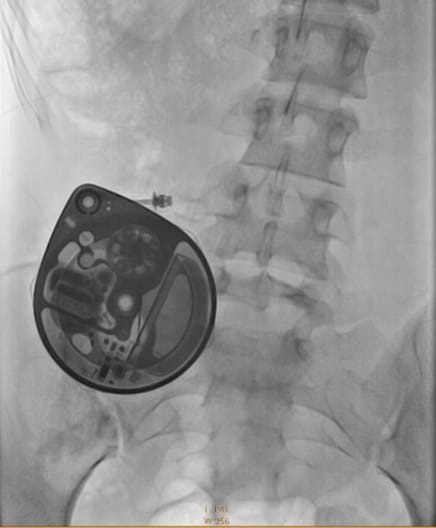

Debido a la severidad de mi dolor, tengo una bomba intratecal de morfina desde el 2021 como tratamiento para controlarlo y mejorar mi calidad de vida. Gracias a ella recuperé cierta movilidad que me ha permitido realizar mis cuidados diarios y la capacidad de trabajar.

En condiciones normales, la bomba intratecal tiene una vida de 7 años, por lo que inicialmente el reemplazo se tenía contemplado para noviembre del 2027. Desafortunadamente esta bomba empezó a fallar el año pasado después de una intervención quirúrgica de emergencia. Tras año y medio tratando de arreglarla, mi calidad de vida ha disminuido considerablemente por el aumento del dolor, y mi única opción es reemplazar todo el equipo.

Aunque llegar a este diagnóstico no fue nada fácil, me permitió empezar tratamientos paliativos para manejar el dolor, entro muchos otros síntomas. Por el desarrollo de mi enfermedad, pasé varios años postrada en cama, con movilidad mínima por la intensidad del dolor. Me vi obligada a dejar la preparatoria y abandonar mi sueño de estudiar medicina. El dolor no mejoraba con ningún tratamiento analgésico (oral, inyectado, cutáneo), y llegó al punto de agotar todas las opciones disponibles. Eso convirtió en candidata para un tratamiento invasivo pero muy efectivo: la implantación de una bomba intratecal de morfina para disminuir el dolor con la menor cantidad de efectos adversos posibles.

En marzo del 2021 me realizaron el procedimiento de implantación de la bomba y, afortunadamente, empecé a responder favorablemente. Mi vida cambió completamente: pasé de vivir en cama incapacitada por el dolor, a poder gozar una calidad de vida relativamente normal. Recuperé mi movilidad con ayuda de muletas, volví a ser capaz de realizar mis cuidados básicos, seguir estudiando, e incluso empezar a trabajar.

Otra consecuencia de esa cirugía fue que mi bomba intratecal dejó de funcionar correctamente. Comenzó a dispensar menos medicamento del indicado por su computadora interna, lo que hizo que el dolor se volviera a ser insoportable. Para compensar esta discrepancia, tuvieron que aumentar la dosis un 60% para volver a controlar mi dolor. Durante meses seguimos los procedimientos recomendados para asegurar que la computadora volviera a dispensar la cantidad correcta, pero no tuvimos éxito. Con el tiempo, la bomba ha continuado administrando cada vez menos medicamento, lo que significa que experimento aún más dolor y la necesidad de aumentar continuamente la dosis para compensar.

En mayo de 2025 se realizó una prueba de catéter para confirmar que éste no estuviera comprometido y que fuera esa la razón de la falla en la bomba. Los resultados mostraron que el catéter no estaba tapado y que sí estaba pasando medicamento. También se realizaron pruebas técnicas en la bomba para verificar el correcto funcionamiento del rotor, comprobando que eso tampoco era el problema. Se decidió entonces esperar 6 meses para ver si su función volvía a la normalidad.

Tristemente, en noviembre de 2025, me confirmaron que el problema de mi bomba no tiene solución y es necesario reemplazar el equipo completo.

In 2021 I had the intrathecal pain pump installed as a last-resort treatment for my severe pain, and it has greatly improved my quality of life. Thanks to the pump I have been able to regain some of my mobility, the ability to care for myself, go back to school, and even start working to sustain myself. Under normal circumstances, an intrathecal pump lasts 7 years, so a replacement was initially planned for November 2027.

Unfortunately, my pump started to fail last year after an emergency spinal surgery, and it is not delivering the amount of medication it should to manage my pain. After more than a year and a half of trying to fix it, unsuccessfully, my quality of life has substantially decreased due to the increased pain. The only solution is to replace the entire system in order to manage my pain again and regain my quality of life.

Another consequence of that surgery was that my intrathecal morphine pump stopped functioning correctly. It began dispensing less medication than its internal computer indicated, causing my pain to become unbearable again. To compensate, my dosage was increased by 60%. For months, we tried every recommended procedure to get the pump to dispense the correct amount, but we were unsuccessful. Over time, the pump has been delivering less and less medication, meaning more pain and ever-increasing dosage adjustments.

In May 2025, I had a catheter test to confirm it wasn't blocked or compromised. Technical tests were also performed on the pump to verify the rotor was functioning. The test showed the catheter was clear and passing medication. The decision was made to wait six months to see if its function would return to normal.

Sadly, in November 2025, they confirmed that my pump has been irreparably damaged and that the entire system would need to be replaced.